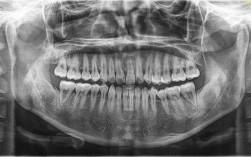

正畸治疗中,部分患者因牙齿拥挤、前突、咬合紊乱等问题需要拔除部分牙齿(即“减数”),以获得足够的间隙实现牙齿排列和咬合功能的改善,而全景片(全景曲面断层片)作为正畸减数前的基础影像检查,是医生制定治疗方案的核心依据,能全面反映口腔颌面部的重...